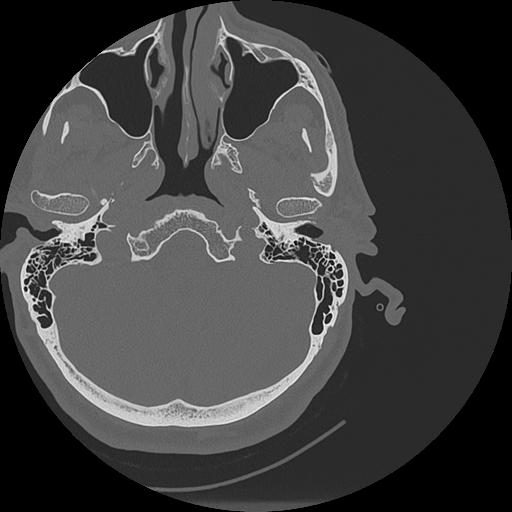

7 HUESO,,Vol,0.5,HUESO,,